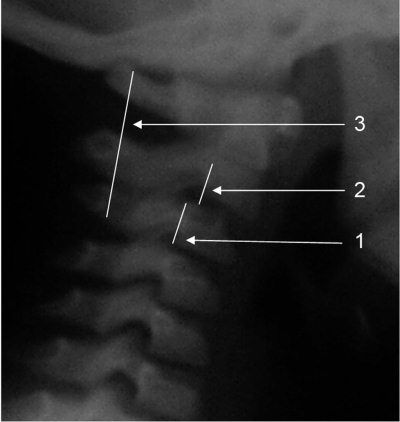

Рис. 4.1. Спондилограмма здорового ребенка 6 лет.

1. Клиновидная деформация тела CIII.

2. Физиологическая гипермобильность CII (псевдолюксация).

3. Линия Swischuk касается основания остистого отростка CII (объяснения см. рис. 4.2